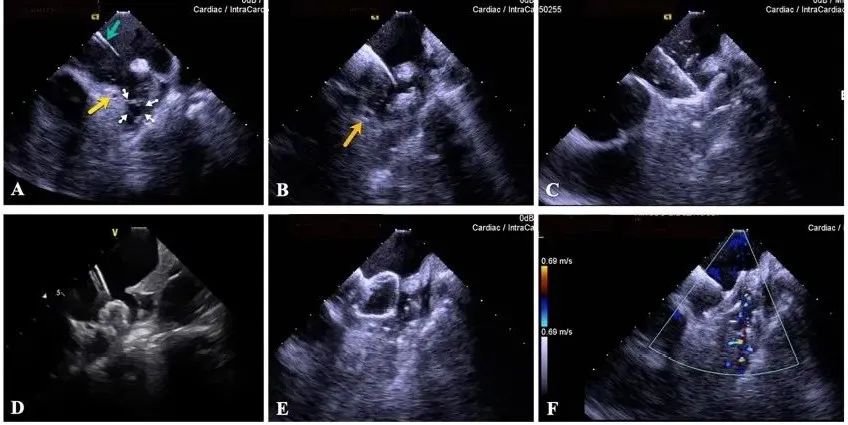

一種與心導(dǎo)管檢查相結(jié)合的超聲心動(dòng)圖診斷新興技術(shù),通過將超聲探頭置于心腔內(nèi)部,發(fā)射并接收超聲信號(hào),來精確獲取心臟解剖結(jié)構(gòu)、心臟血流動(dòng)力學(xué)等信息的實(shí)時(shí)成像。與其他影像技術(shù)相比,ICE技術(shù)具有操作簡單、無輻射、安全性高、手術(shù)效率高、實(shí)用等優(yōu)勢(shì),ICE在很大程度上有望取代經(jīng)食道超聲心動(dòng)圖(TEE),成為電生理和結(jié)構(gòu)性心臟病領(lǐng)域的理想成像方式。

目前ICE技術(shù)已被應(yīng)用于左心耳封堵、房顫射頻消融、二尖瓣成形、房間隔缺損封堵等多種心臟介入手術(shù),應(yīng)用場景主要圍繞心臟電生理、結(jié)構(gòu)性心臟病等領(lǐng)域,目前以電生理應(yīng)用為主。數(shù)據(jù)顯示,我國結(jié)構(gòu)性心臟病介入器械市場規(guī)模已從2017年的4億元增長至2021年的20億元,年復(fù)合增長率達(dá)48.3%;預(yù)計(jì)到2025年,該市場規(guī)模將達(dá)到104億元,可以預(yù)見ICE市場規(guī)模也將同步高速增長,未來市場發(fā)展空間廣闊。